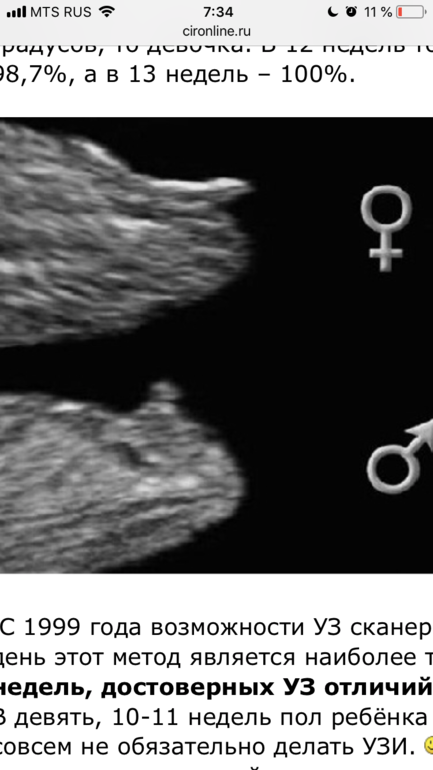

врач сказал, что девочка. я в сомнениях, не понимаю особо, как отличать, на таком сроке они вроде почти одинаковые

Где зачатки половых органов там разный угол